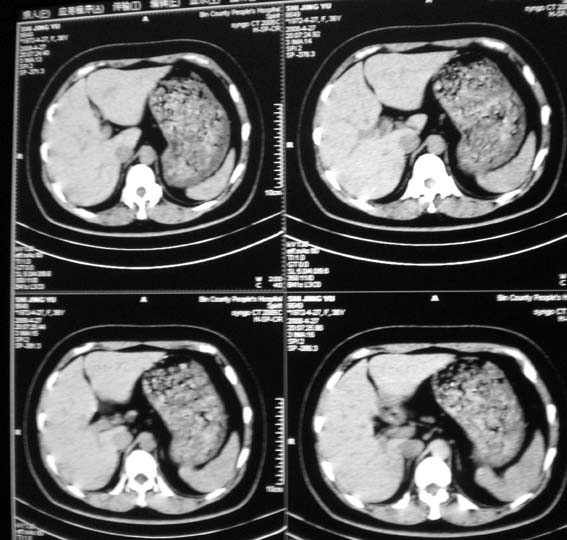

标题: CT13126:腰痛,肾区痛。

女,36岁,腰痛,肾区痛曾有肾囊肿史。

右肾有囊肿,余未件异常

上腹部平扫未见明显异常。